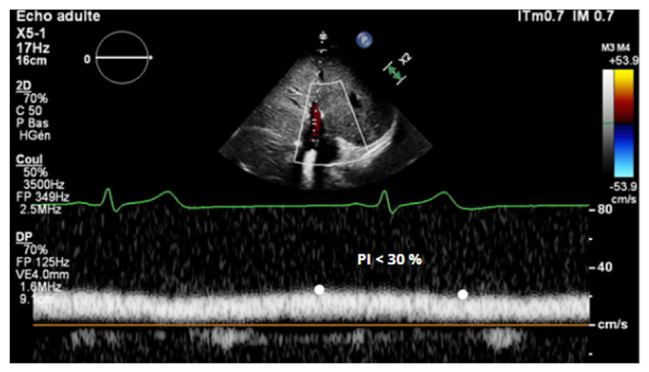

Abstract Image